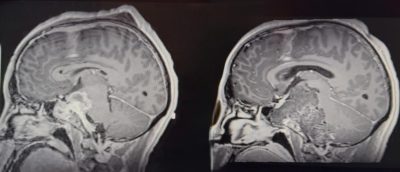

نجح فريق طبي سعودي في مستشفى الملك فهد بجدة عضو تجمع جدة الصحي الثاني بقيادة د. هاني القرشي في استئصال ورم حبلي نادر ومعقد من قاع الجمجمة، خلال ثلاث عمليات جراحية متتالية استغرقت ٣٥ ساعة. الورم كان ضاغطًا على جذع الدماغ والأعصاب القحفية، وتعامل معه الفريق بتقنيات جراحية متقدمة لا تُجرى إلا في مراكز عالمية محدودة، ولله الحمد المريض تعافى وعاد لحياته الطبيعية دون أي عجز عصبي يذكر.